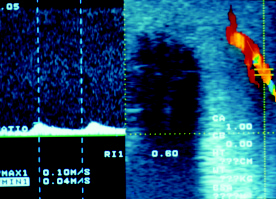

La ecografía doppler duplex, que permite evaluar el flujo arterial y venoso en el pene, los cambios de calibre de la arteria intracavernosa y el comportamiento espectral en el complejo sístole/diástole.

Se trata básicamente de evaluar la morfología espectral de las arterias intracavernosas, que pasan de baja, en reposo, a alta resistencia, en erección.

- Expresión de sístole y diástole en un lecho de baja Resistencia (R).

- Presión intracavernosa de igual presión que la diástole sistémica que, subsiguientemente, no se representa.

- Diástole negativa, porque el cuerpo cavernoso presenta una Presión superiora la diastólica sistémica, con lo que la sangre refluye durante la diástole hasta que vuelve a ser empujada positivamente en el siguiente latido sistólico.

- Ensanchamiento de la honda y descenso de la velocidad en sístole, expresión de la alta resistencia en ambos tiempos del ciclo cardíaco.

Ecografía doppler en varón sano. Se aprecia la alta velocidad en sístole y la inversión en diástole de la arteria cavernosa